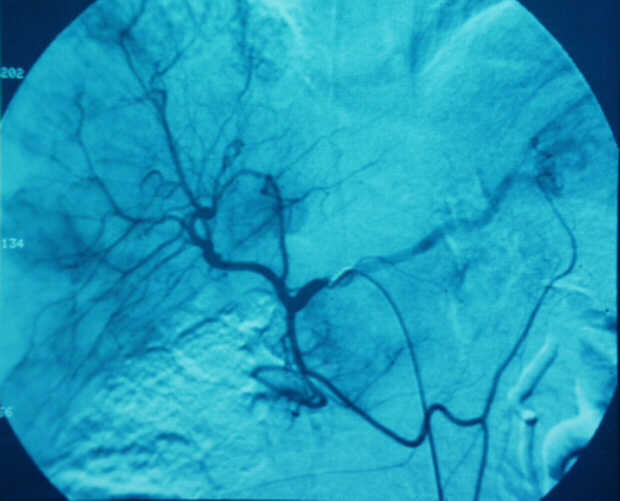

Pancreatic Head Mass: What Can Be Done?

Diagnosis: Angiography

Giuseppe Morelli Coppola, Raffaella Niola, Franco Maglione

Unità Operativa di Radiologia Vascolare ed Interventistica, Azienda Ospedaliera "A. Cardarelli". Napoli, Italy